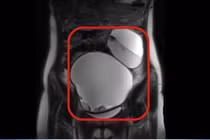

Khoa Phụ sản, Bệnh viện Đa khoa khu vực Bắc Quang (Hà Giang) vừa tiếp nhận bệnh nhân N.T.X. (36 tuổi) nhập viện trong tình trạng đau bụng dữ dội vùng hạ vị, khởi phát đột ngột và tăng dần, kèm buồn nôn và nôn. Khám lâm sàng ghi nhận phản ứng đau rõ vùng hạ vị và phần phụ phải. Siêu âm cho thấy khối phần phụ phải kích thước lớn, cấu trúc không đồng nhất, phù nề rõ.

Bệnh nhân được chỉ định phẫu thuật nội soi cấp cứu. Trong mổ, ê-kíp ghi nhận phần phụ phải bị xoắn hai vòng. Do tổ chức phần phụ đã hoại tử, không còn khả năng bảo tồn, các bác sĩ buộc phải cắt bỏ phần phụ phải để tránh biến chứng nguy hiểm.